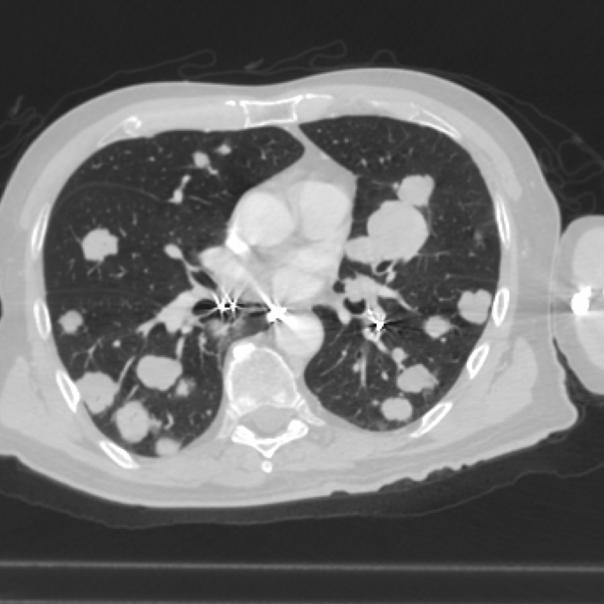

Фотографии и снимки КТ легких без контрастных веществ